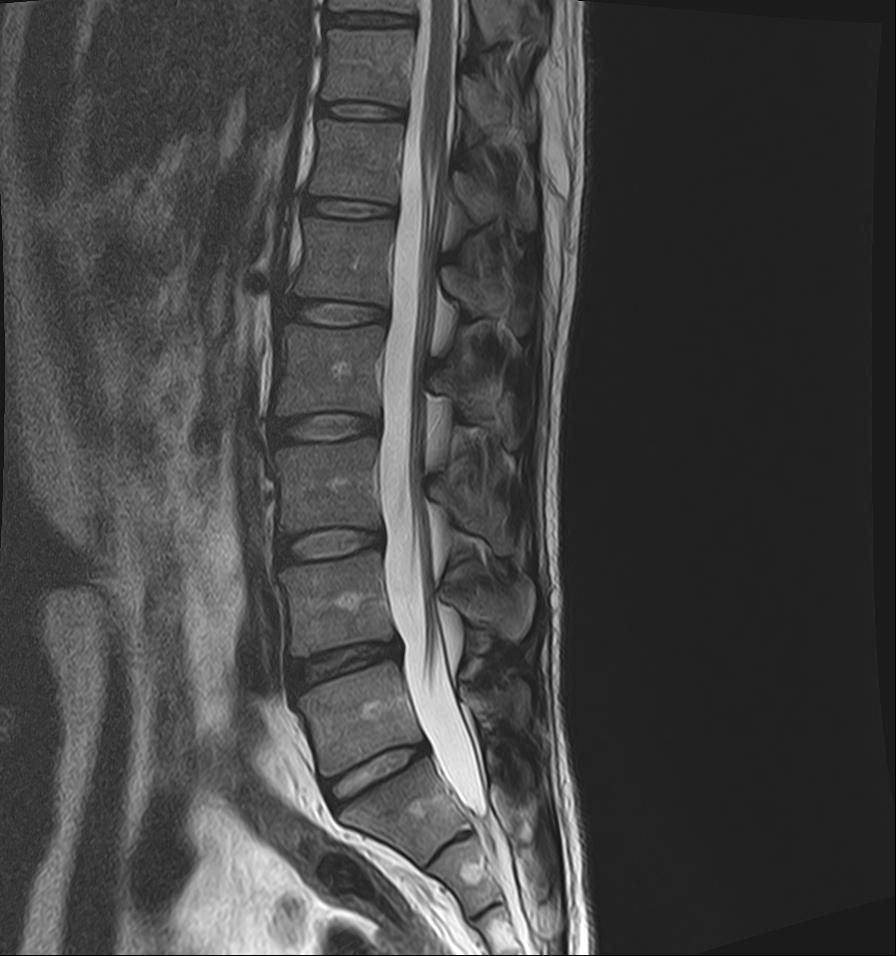

21년도와 24년도 각각 찍은 L spine 사진입니다.

2024년 영상